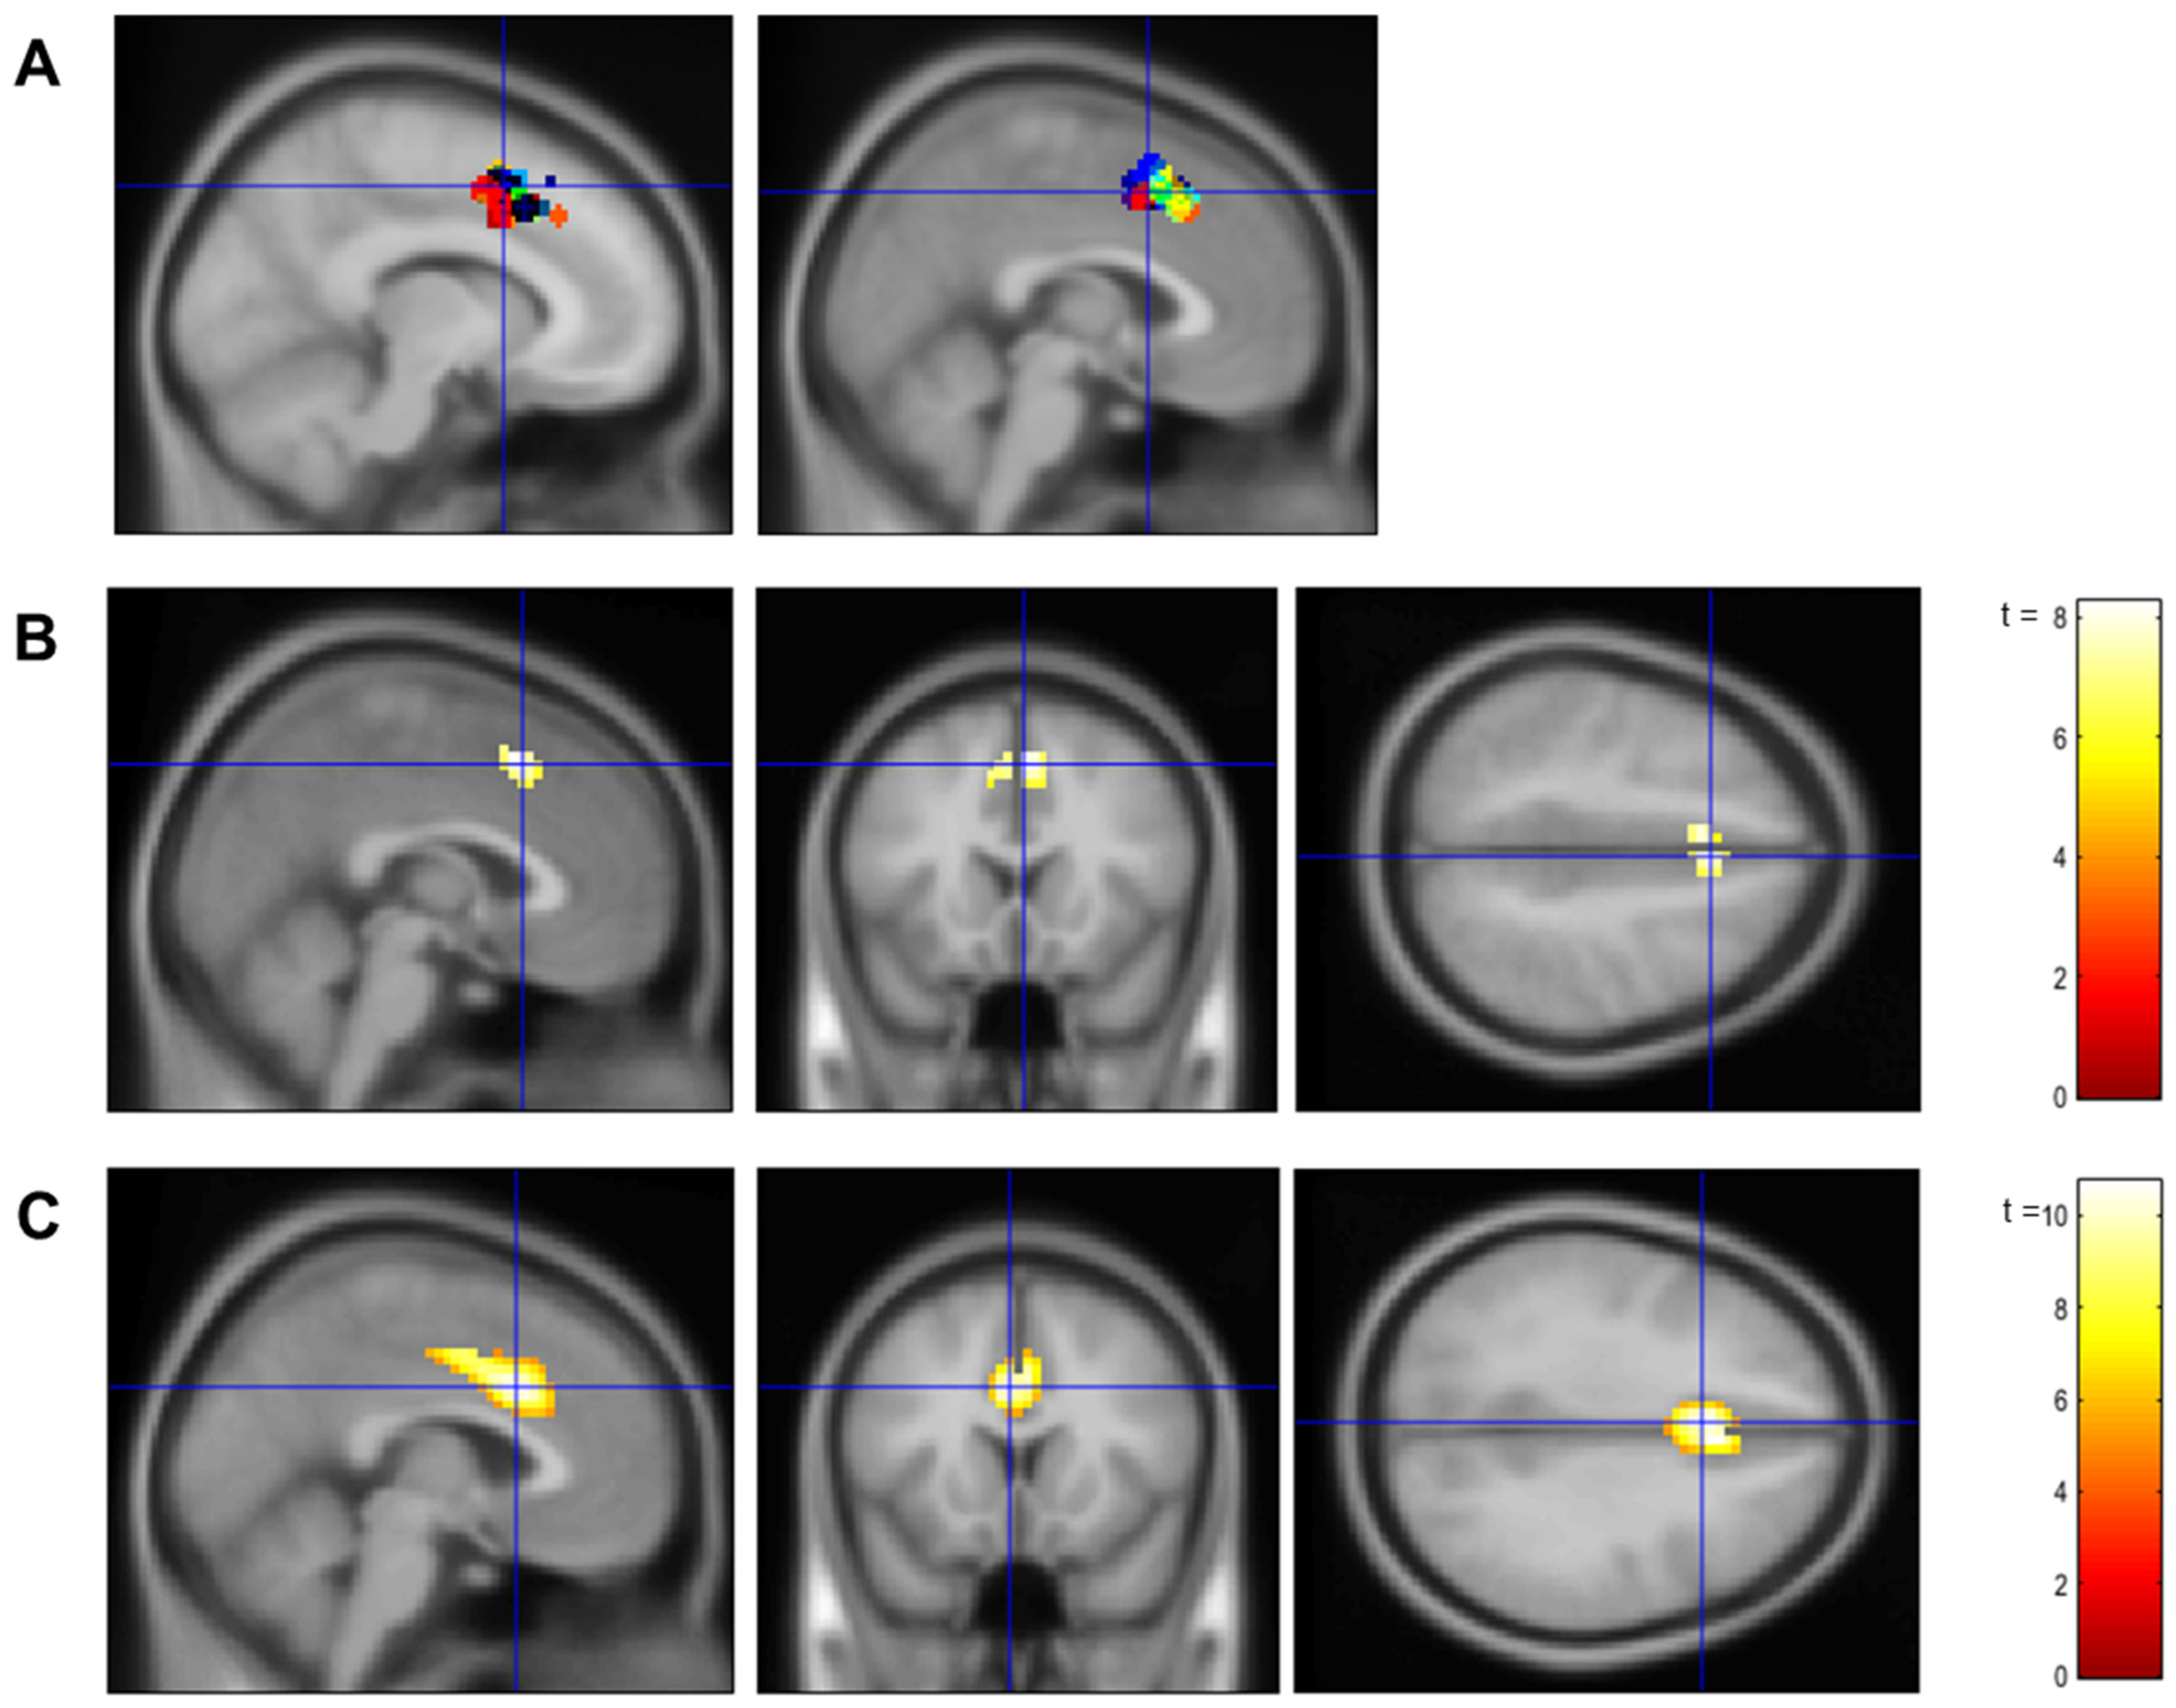

2.6.1. Localizer

2.6.2. Neurofeedback Training

3.1. Confirmation of dACC Involvement in the Localizer Task and the Neurofeedback Training